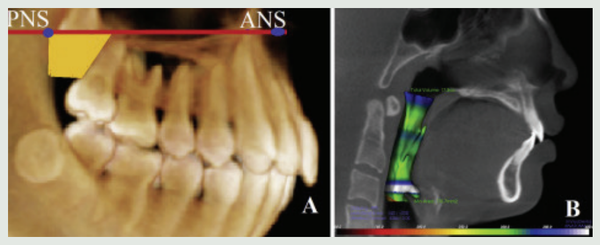

국윤아 교수 연구팀은 서울성모병원 치과병원에서 2009년부터 2013년까지 상악 치열을 후방 이동하는 치료를 받은 2급 부정교합 청소년 환자 20명(평균 나이 12.9 세)을 대상으로 치료 종료 후 3년의 유지기간 동안 상악결절(위턱 사랑니 뿌리 옆 솟은 부위) 및 기도공간의 부피 변화에 대해 조사했다. 대조군은 교정치료를 받지 않은 청소년 환자 20명(평균 나이 19.3세)으로 선정했다.

연구팀은 치료 전 MCPP 치료 직후 3년 후의 고화질 치과용 CT(CBCT-cone- beam computed tomography) 영상 이미지를 비교해 상악결절 부피 및 기도공간 부피 변화를 측정했다. 그 결과 해당 환자들은 치료 전에 그리고 MCPP를 이용한 상악치열의 후방이동 치료 후 3년 이상의 유지기간 시의 CBCT를 촬영했고 해당 CBCT를 통해 상악결절의 부피와 기도공간의 부피 변화를 측정했다.

MCPP 치료군은 기도공간에 있어 치료 후 유지기간 동안 유의할만한 변화량을 보이지 않았으며 대조군과도 차이가 없었다.

연구결과는 2급 부정교합을 가진 청소년 환자에서 MCPP 교정치료가 기도공간 및 골격적으로 부정적인 영향을 미치지 않는 효과적인 치료방법임을 시사했다. 특히 교 정치료로 인해 치열이 뒤로 밀리면 기도가 좁아지지 않을까 우려하기 쉬운데 골격적 이상이 없다는 점이 입증돼 기도 공간이 좁아질 때 생길 수 있는 수면무호흡증과도 무관하다는 점이 주목할 만하다.